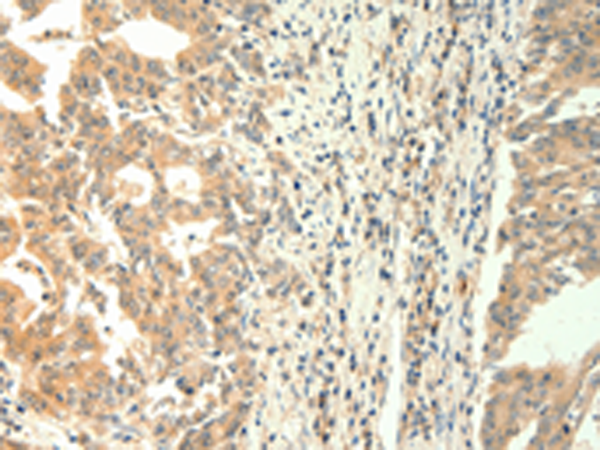

分类: 科研抗体货号: P04568别名: ANTP; HOX1; HOX1A; HOX1.1应用: IHC反应种属: Human, Mouse